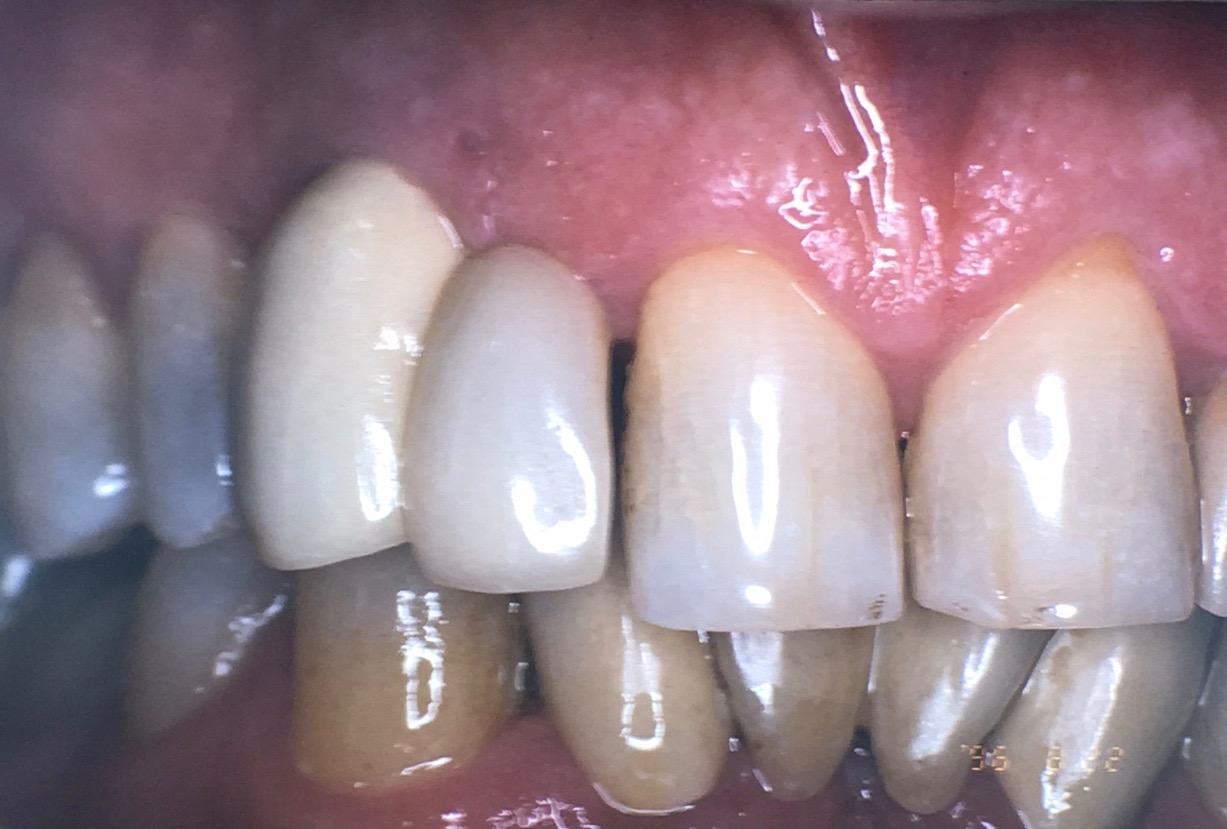

Fig 18. In 1999, teeth Nos. 8 and 9 had the same length with even gingival margins.

Figure 18

Fig 19. In 2016, downward growth of tooth No. 8 could be observed with uneven gingival margins of Nos. 8 and 9.

Figure 19